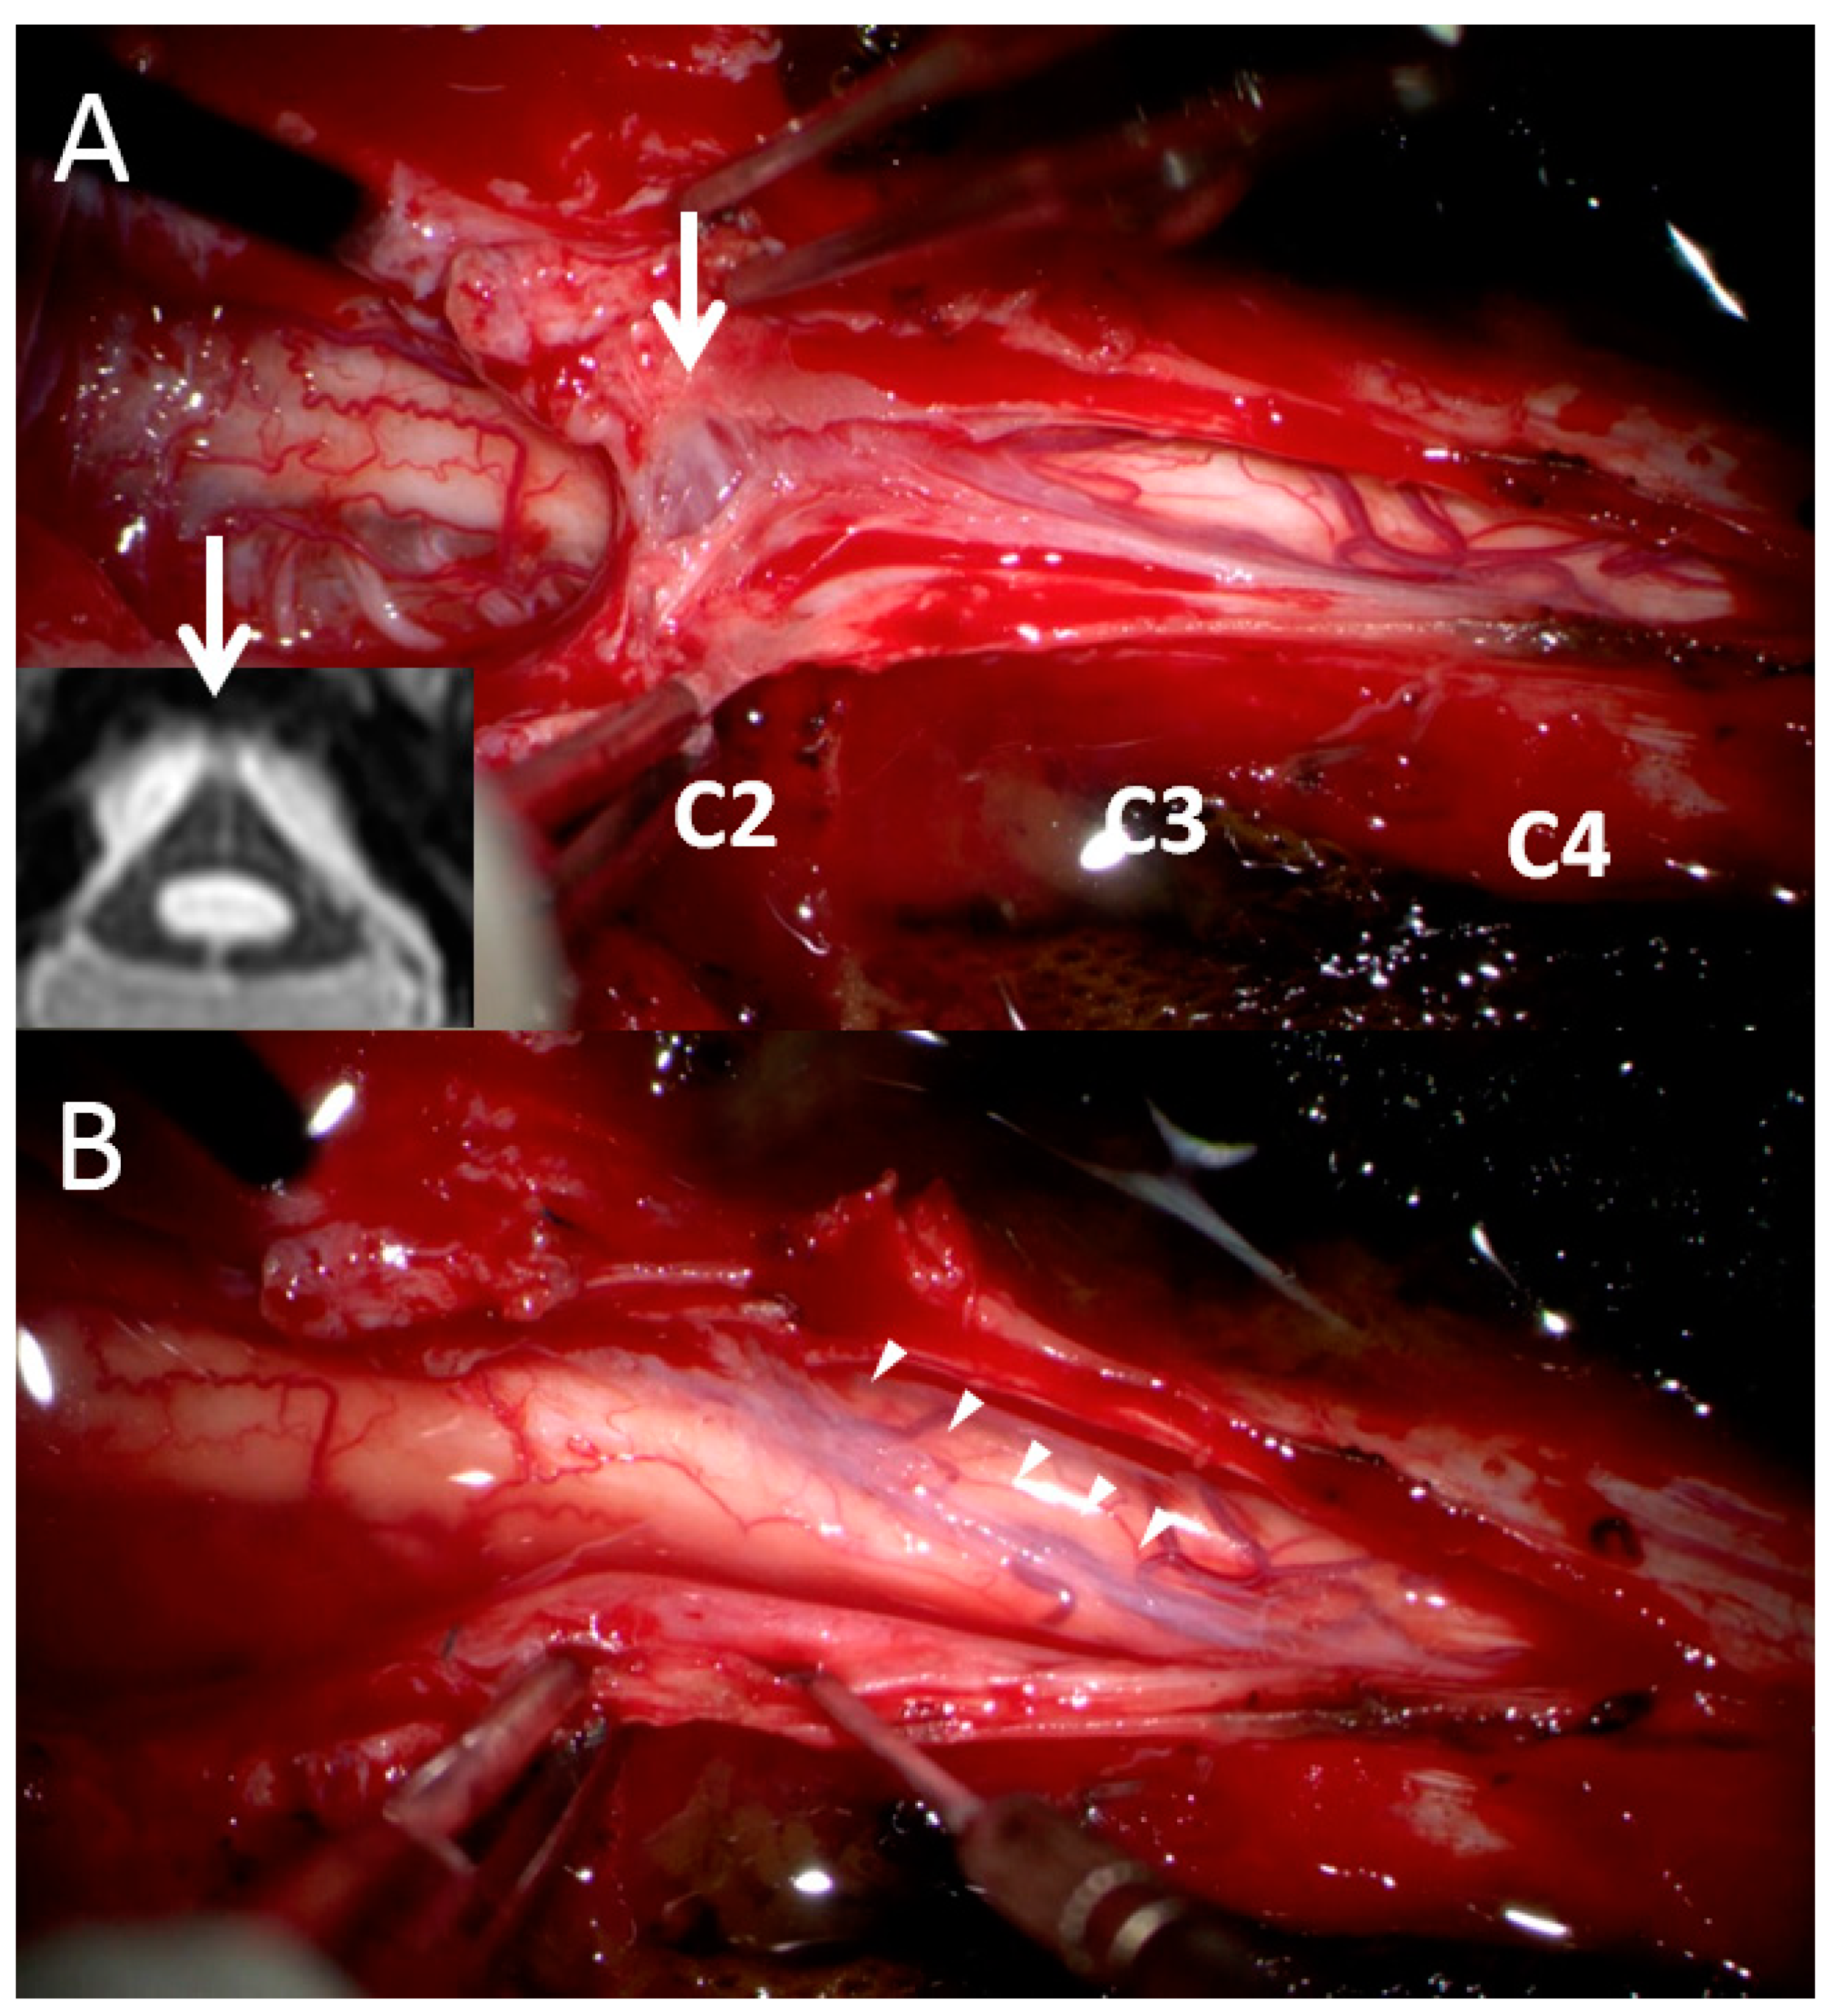

In order to address the postoperative adhesive arachnoiditis, a third surgery was performed. This surgery involved laminoplasty of C3–4 and extensive duroplasty from the suboccipital region to the C4 level. During the surgery, a thick arachnoid band was discovered. This band tethered the cord at the C2 level, confirming the presence of the delta cord sign. After separation of the arachnoid band, the syrinx collapsed, and the arachnoid space was no longer obstructed (Figure 3). After 1 year of postoperative follow-up, the syrinx collapsed, and an improvement of the edematous change in the spinal cord was observed (Figure 4). In addition, the patient’s functional status improved, with his mJOA score increasing from 10 to 11 and his Barthel Index score increasing from 50 to 60. Thus, he was able to walk with the assistance of a cane and perform the majority of his daily tasks, albeit with some dependency. He continued to experience residual paresthesia in his upper limbs and left lower limb.

Figure 3.

Surgical findings. (A) At the C2 level, a thick arachnoid band (white arrow) extended to the C4 level and obstructed CSF flow between the cranial and caudal sites. This finding was consistent with our previous MRI finding of the delta cord sign (we rotated the axial MRI view 180° to match the surgical finding). (B) After the release of the arachnoid band (arrow heads), the cord collapsed and connected CSF flow from the cranial and caudal sites.